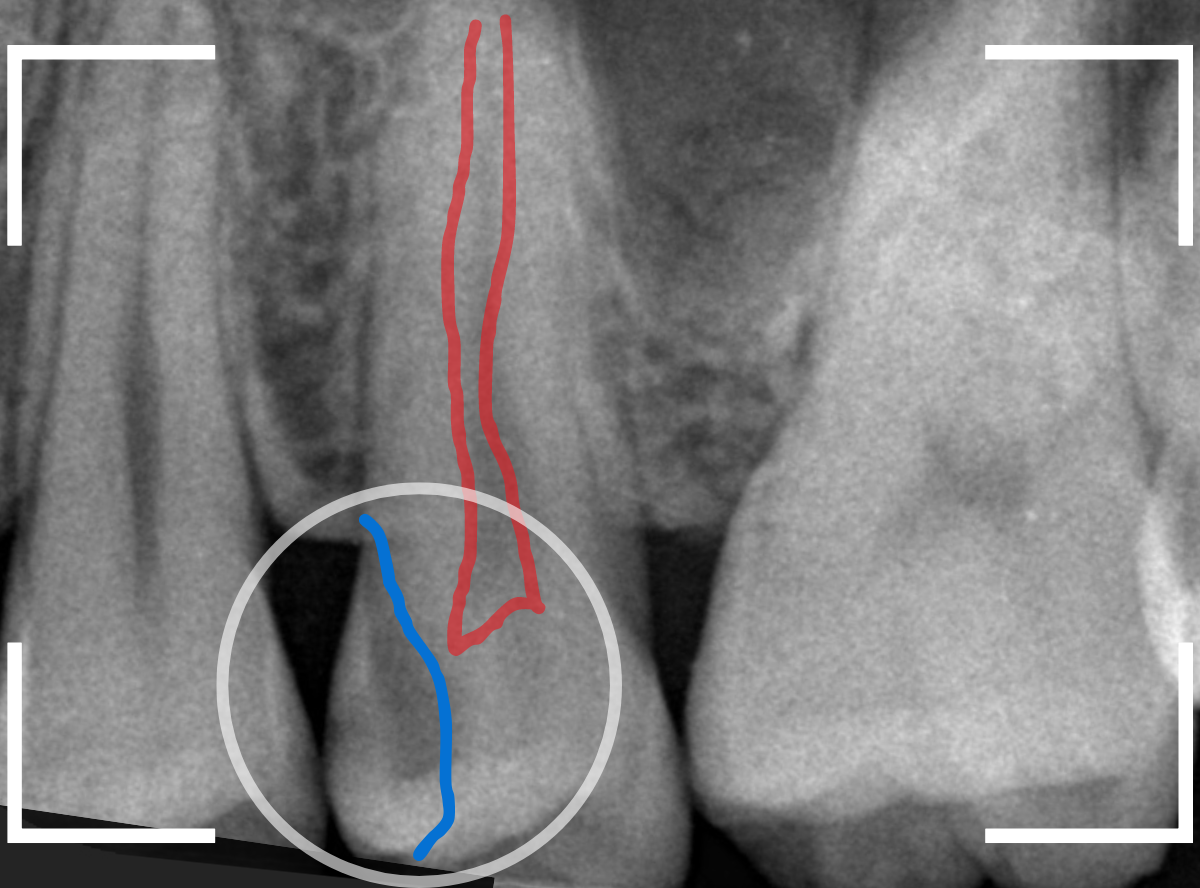

Case.21 神経に達しそうな2本の大きな虫歯

上の小臼歯の側面が明らかに虫歯になっている患者さんです。

患者さんは特に症状を感じてなさそうですが、恐らくは中で大きな虫歯になっているでしょう。

このように、自覚症状からだけでは虫歯の状況は診できません。

レントゲン写真で確認します。

青い線が歯の神経、赤い線が虫歯と思われる部分です。

2本とも、神経に達してしまいそうな大きな虫歯であると思われます。

まず、奥の歯のつめものを外してから、虫歯の治療を開始します。

手前の歯が大きな虫歯が見えてきました。

神経に達してしまいそうな虫歯ですので、ある程度削ったところで、少しずつエキスカという道具で掻き出すようにして、虫歯を除去します。

虫歯は歯を溶かして進行しますので、骨よりも固い歯もちょっと掻き出すとボロボロと崩れるようになってしまっています。

かなり虫歯を除去したところで、手前の歯は神経が顔を出してしまいました(露髄といいます)。

神経を除去する治療が必要かもしれないです。

全ての虫歯を除去したところです。

幸い、後ろの歯は薄皮一枚のところで神経まで達していない虫歯ですんでいましたが、大きな虫歯だった事には変わりありません。

いつものように、神経が痛み出さないように祈りつつ、お薬で保護して経過観察します。

虫歯は症状からだけでは判断できませんが、定期受診によって、このような大きな虫歯の処置は避けられる事がほとんどです。